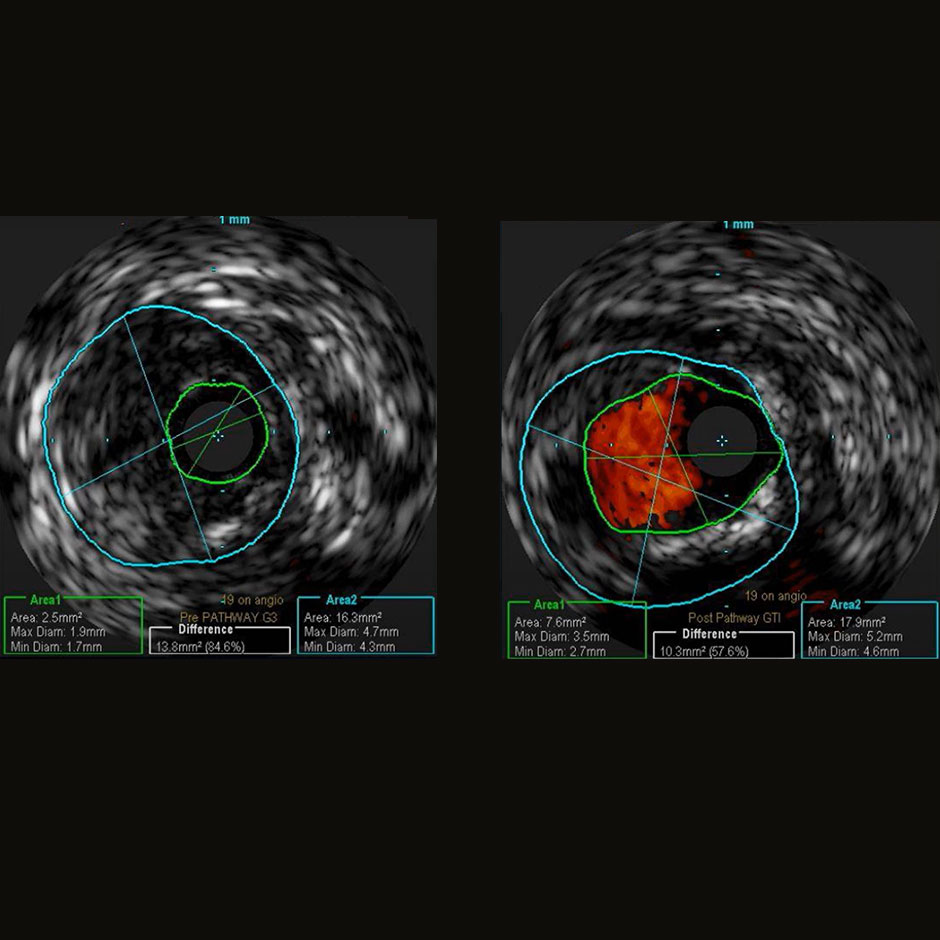

Case Example from Jetstream Calcium Study

Distal SFA/Proximal Popliteal*

Successful debulking with the Jetstream Atherectomy System in a distal right SFA/proximal popliteal artery lesion. The pre-atherectomy IVUS image reveals a lumen area of 2.5 mm². The post-atherectomy images reveal a lumen area of 7.6 mm² and impressive debulking with Jetstream Atherectomy even before adjunctive therapy.

*Results from case studies are not necessarily predictive of results in other cases. Results in other cases may vary.

Pre-procedure CTO of right distal SFA/proximal popliteal. Baseline IVUS measurement reveals area of 2.5 mm² Pre-procedure CTO of right distal SFA/proximal popliteal. Baseline IVUS measurement reveals area of 2.5 mm²

Standalone Jetstream result (prior to PTA) reveals an IVUS measurement of 7.6 mm² Standalone Jetstream result (prior to PTA) reveals an IVUS measurement of 7.6 mm²